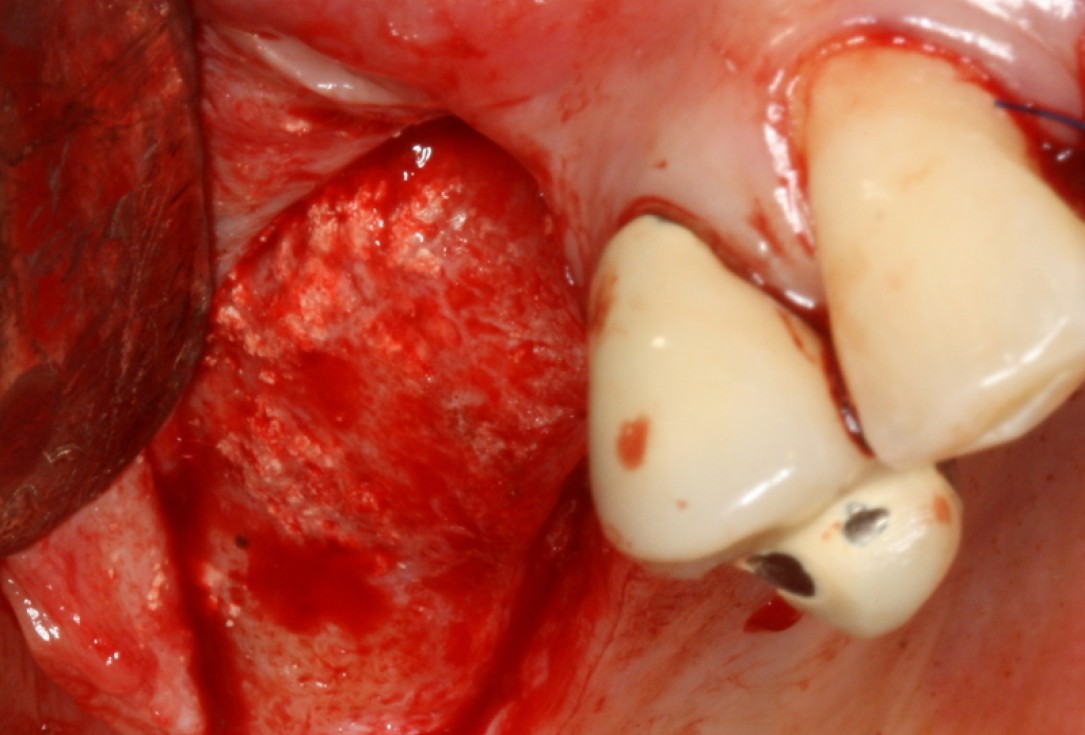

08/20 - Surgical presentation of the alveolar ridgeGBR with maxresorb® & Jason® membrane - Prof. Dr. Dr. D. Rothamel